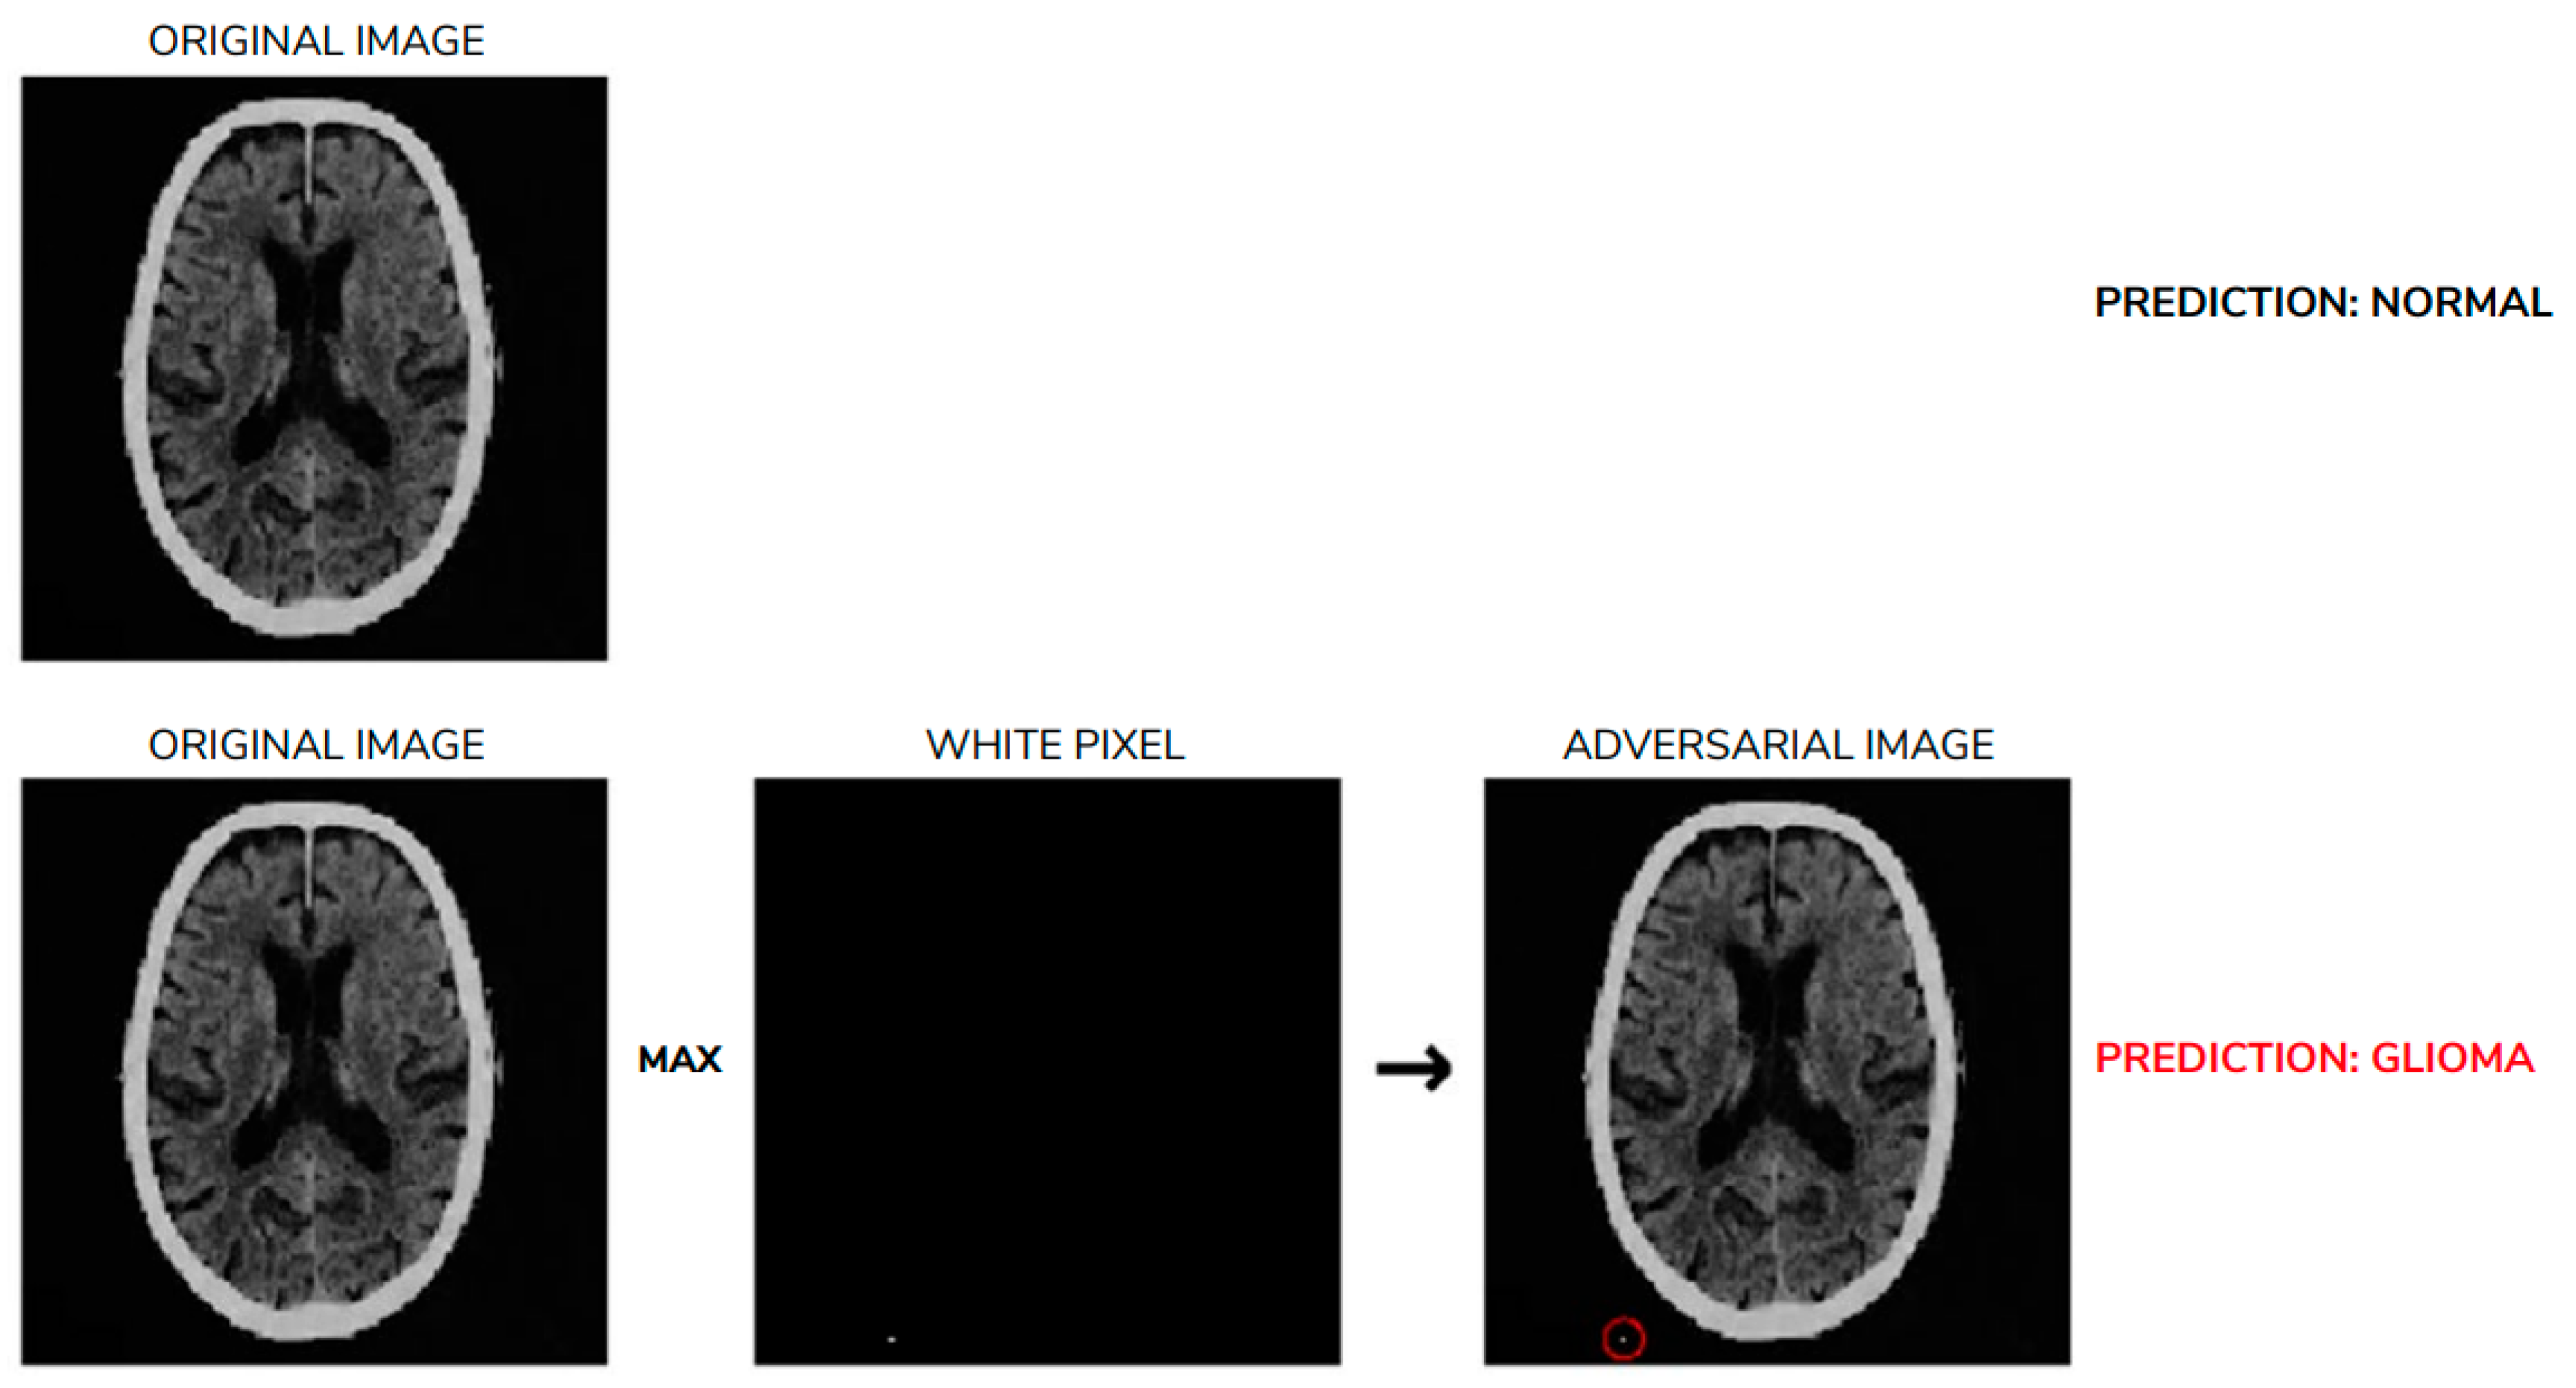

6.2. Heightened Sensitivity to Perturbations in AI-Generated Diagnosis

- Joel, M.Z.; Umaro, S.; Chang, E.; Choi, R.; Yang, D.X.; Duncan, J.S. Using adversarial images to assess the robustness of deep learning models trained on diagnostic images in oncology. JCO Clin. Cancer Inform. 2022, 6, e2100170. [Google Scholar] [CrossRef]

- Tsai, M.-J.; Lin, P.-Y.; Lee, M.-E. Adversarial Attacks on Medical Image Classification. Cancers 2023, 15, 4228. [Google Scholar] [CrossRef] [PubMed]

- Tajak, W.; Nurzynska, K.; Piórkowski, A. Vulnerability to One-Pixel Attacks of Neural Network Architectures in Medical Image Classification. Bio-Algorithms Med. Syst. 2025, 21, 58–70. [Google Scholar] [CrossRef]